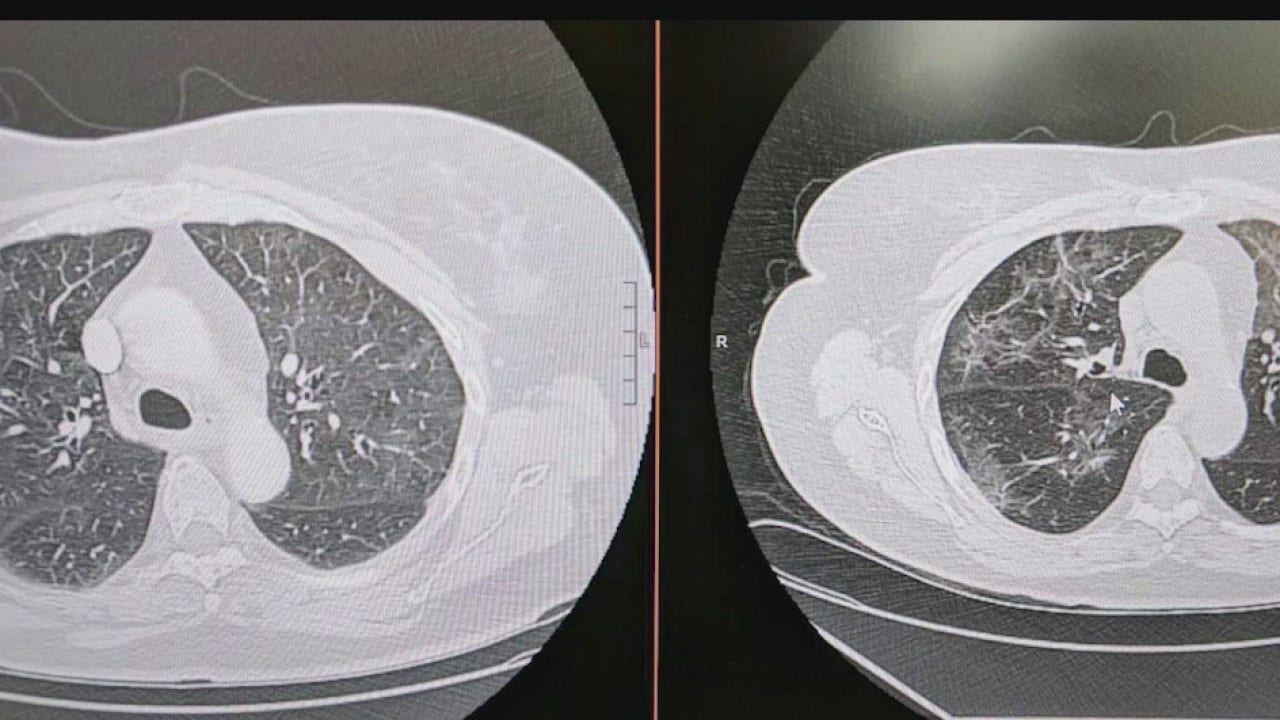

Seen in a scan of lungs that have been through COVID-19, a haze of white patches caused by the virus, according to Dr. Heemesh Seth, a pulmonologist with HonorHealth.

He says the white haze represents the "inflammation the virus is causing inside the lung" and that this type of inflammation is not seen in smokers' lungs.